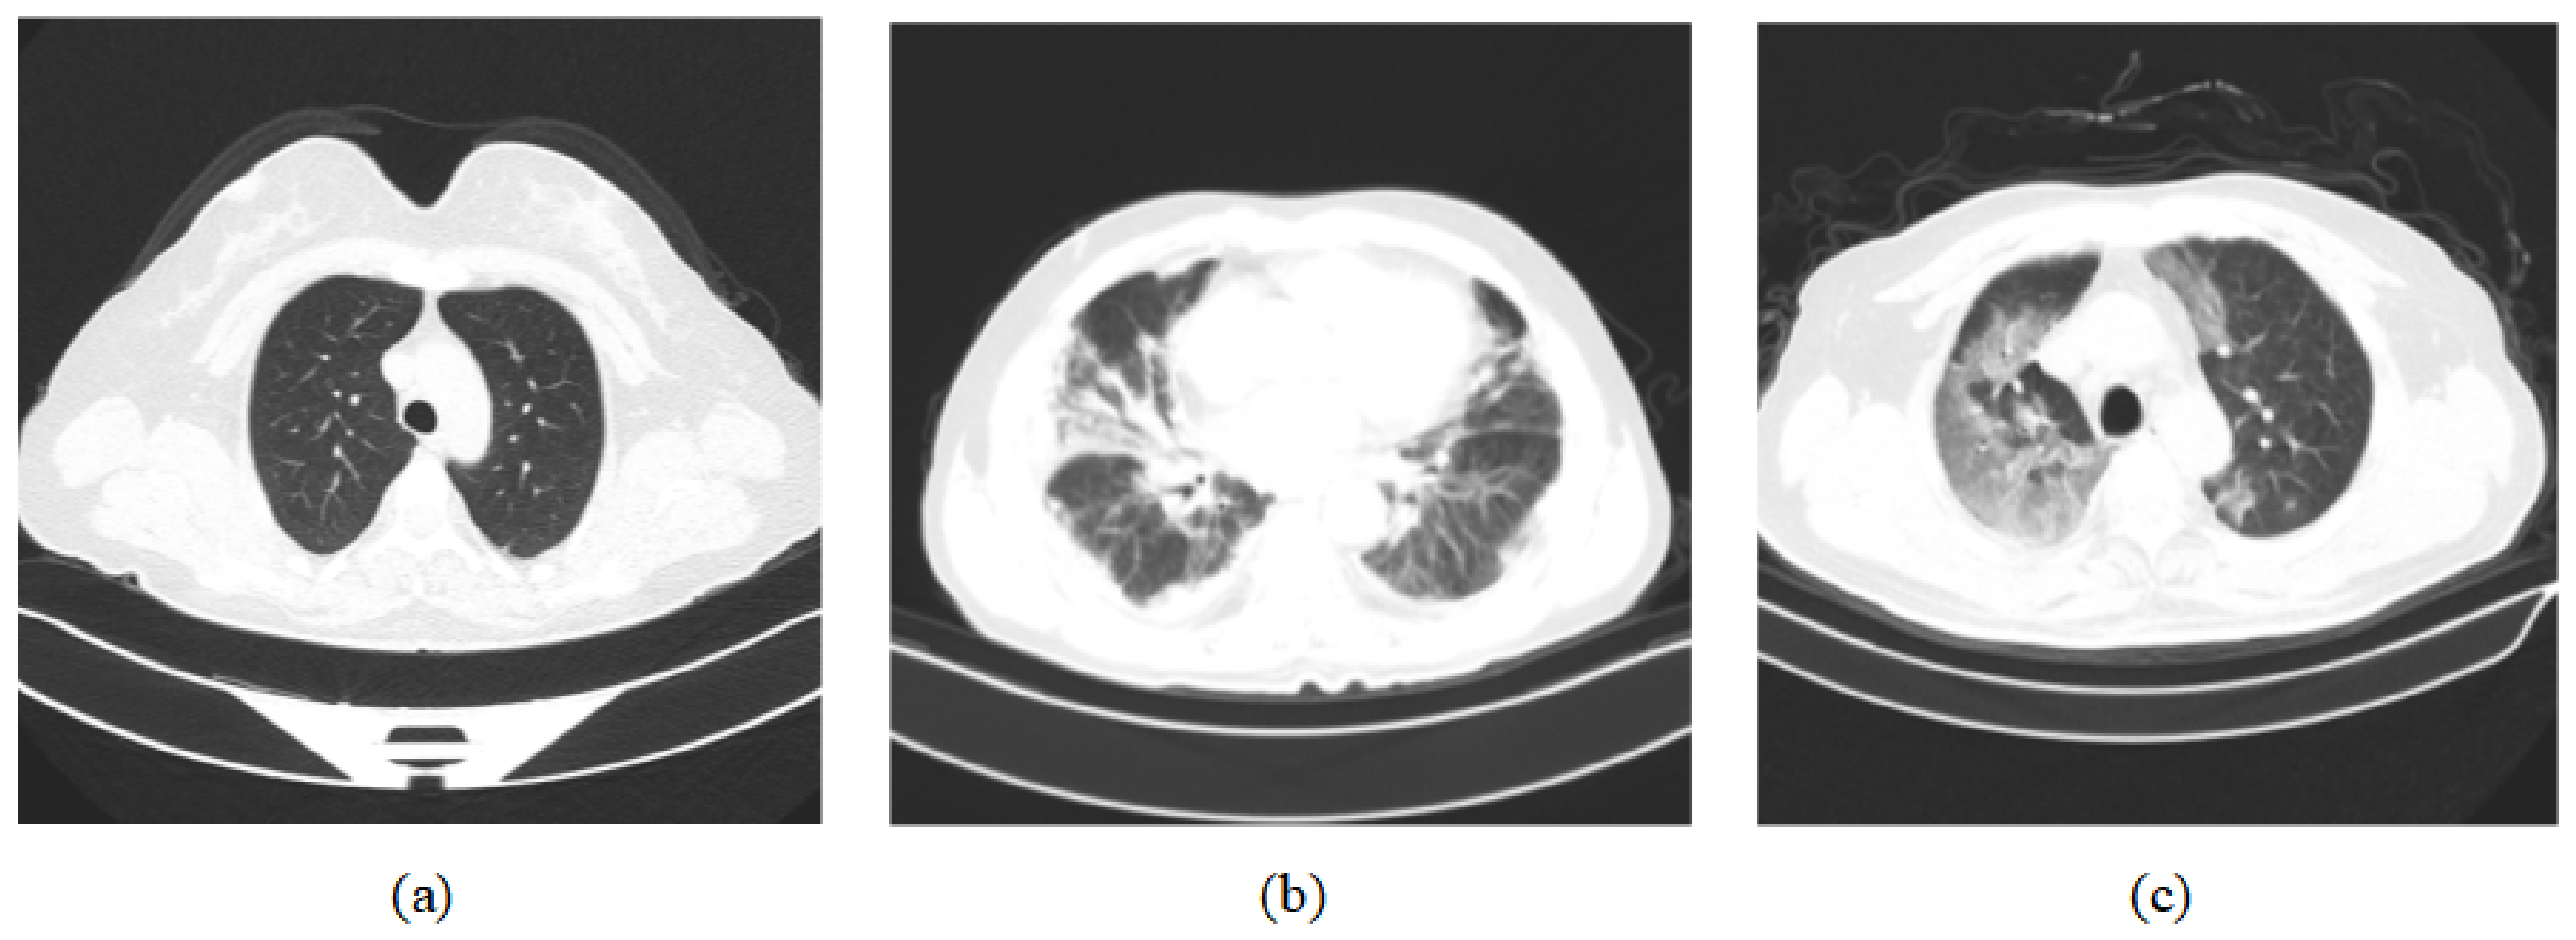

However, because of the disadvantage that MSR often suffers from “halo” artifacts and low contrast, we first converted the CT images from RGB to grayscale to reduce the amount of computation, and then used the CLAHE [46] method to enhance the contrast of the image, as well as to avoid the loss of image details. Compared to the traditional adaptive histogram equalization (AHE) method, CLAHE is more able to overcome the problems of AHE, such as amplified noise regions in the image, and can better extract the lesion areas. The results of the image preprocessing are shown in Figure 3.

Figure 3.

(a) Original images; (b) processed images [11,12].